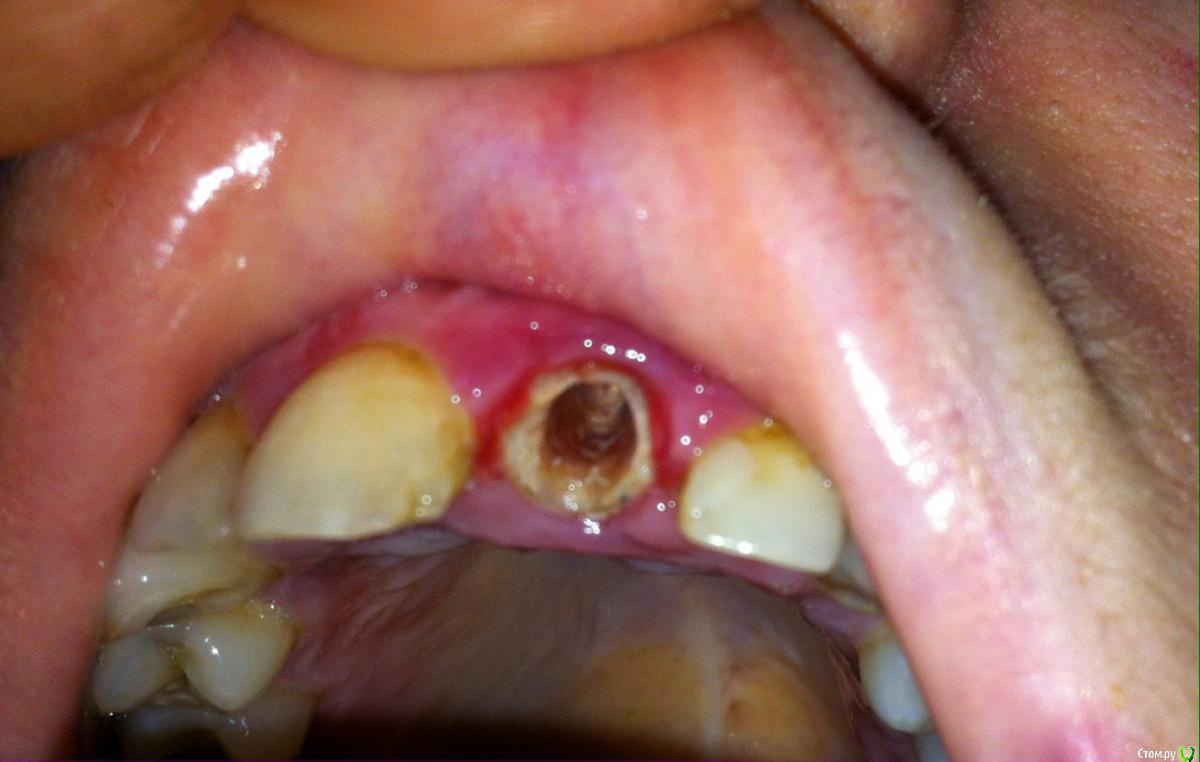

l_yulia Опубликовано 21 июля, 2015 Поделиться Опубликовано 21 июля, 2015 С этим зубом долгая история. 7 лет назад у меня там была киста и одновременно беременность, а когда беременность закончилась, а киста была вылечена, то в оставшийся корень вставили стекловолоконный штифт и на него коронку. Коронка металлокерамическая, врач мне сказала тогда, что поставить безметалловую керамику нельзя (видимо им просто почему-то так было удобнее). Коронка была толще чем мой собственный зуб и именно это стало причиной того что в конце-концов коронка вместе со штифтом вывалилась (я ее как бы все время толкала нижними зубами).Так как финансовой возможности в момент выпадения коронки никакой не было от слова совсем, то я решила приклеивать его каждый день на корегу, и регуляно полоскать антисептиками. Но на прошлой неделе, когда я ела персик, коронка внезапно отклеилась, а я не сразу заметала и продолжила кусать персик, потом услышала хруст и поняла, что придется уже решать как-то проблему. Скорее всего я все таки сломала корень, так как потом 2 дня были не очень приятные ощущения в области зуба.В прошлую пятницу и субботу я записалась в 3 стоматологических клиники на консультацию на счет имплантации. Я хотела одномоментную с удалением корня имплантацию, и желательно чтоб можно было сразу установить временную коронку, так как зуб передний.И вот что мне сказали в разных местах:1) Сказали, что да, можно поставить сразу. В той клинике используют только 2 системы имплантов ("Implantium" и "SuperLine"). И они мне посчитали "SuperLine". Правда сказали, что о том возможно ли будет нагружать имплант сразу станет понятно только после удаления, глядя на состояние кости, плотная она или рыхлая. И еще сказали, что обязательно потребуется пересадка кусочка кожи с неба на десну. 2) Здесь ставят разные системы ( "Miss", "Alpha bio", "AstraTech", "Implantium" и "SuperLine"). Я сказала, что думала про alpha bio и мне посчитали его, но потом врач мне аргументированно объяснил, что чтоб имплант можно было сразу нагружать он должен быть длинее собственного корня зуба, а этому требованию соответствует только "SuperLine" и что потребуется подсыпка костной ткани. И он не возражал против временной коронки и был категорически против протеза бабочки, мол он все сосочки примнет.3) Здесь ставят разные системы ( AlphaBio и MIS, Xive и Impro, Straumann, Nobel Biocare и Biohorizons, Astra Tech) Врач сказал мне, что нет никакой разницы какой длины сам имплант и посчитал мне MIS. Напугал меня тем, что при удалении оставшегося корня зуба у меня не останется передней стенки (если поставить имплант одномоментно, то он будет просвечивать) и лучше будет, если сначала удалить зуб, а имплант поставить через 2 недели, когда кровяной сгусток видоизменится в костную ткань. Он был категорически против сразу ставить временную коронку и был за протез бабочку, когда я спросила про сосочки, то он сказал, что мы так сделаем протез, что ничего не примнем.А теперь мне хочется здесь на форуме получить независимую консультацию и понять, какой имплант лучше, действительно ли он должен быть длинее собственного корня или это не имеет никакого значения?Правда ли что у меня после удаления не останется переднней стенки кости?Кто из врачей, которые меня консультировали , более компетентный? КТ у меня есть. Прикрепляю 2 снимка, может на втором что-то лучше видно. один 17.07.2015, а второй примерно полугодовой давности. И фото.17.07.2015 конец 2014фото Ссылка на комментарий